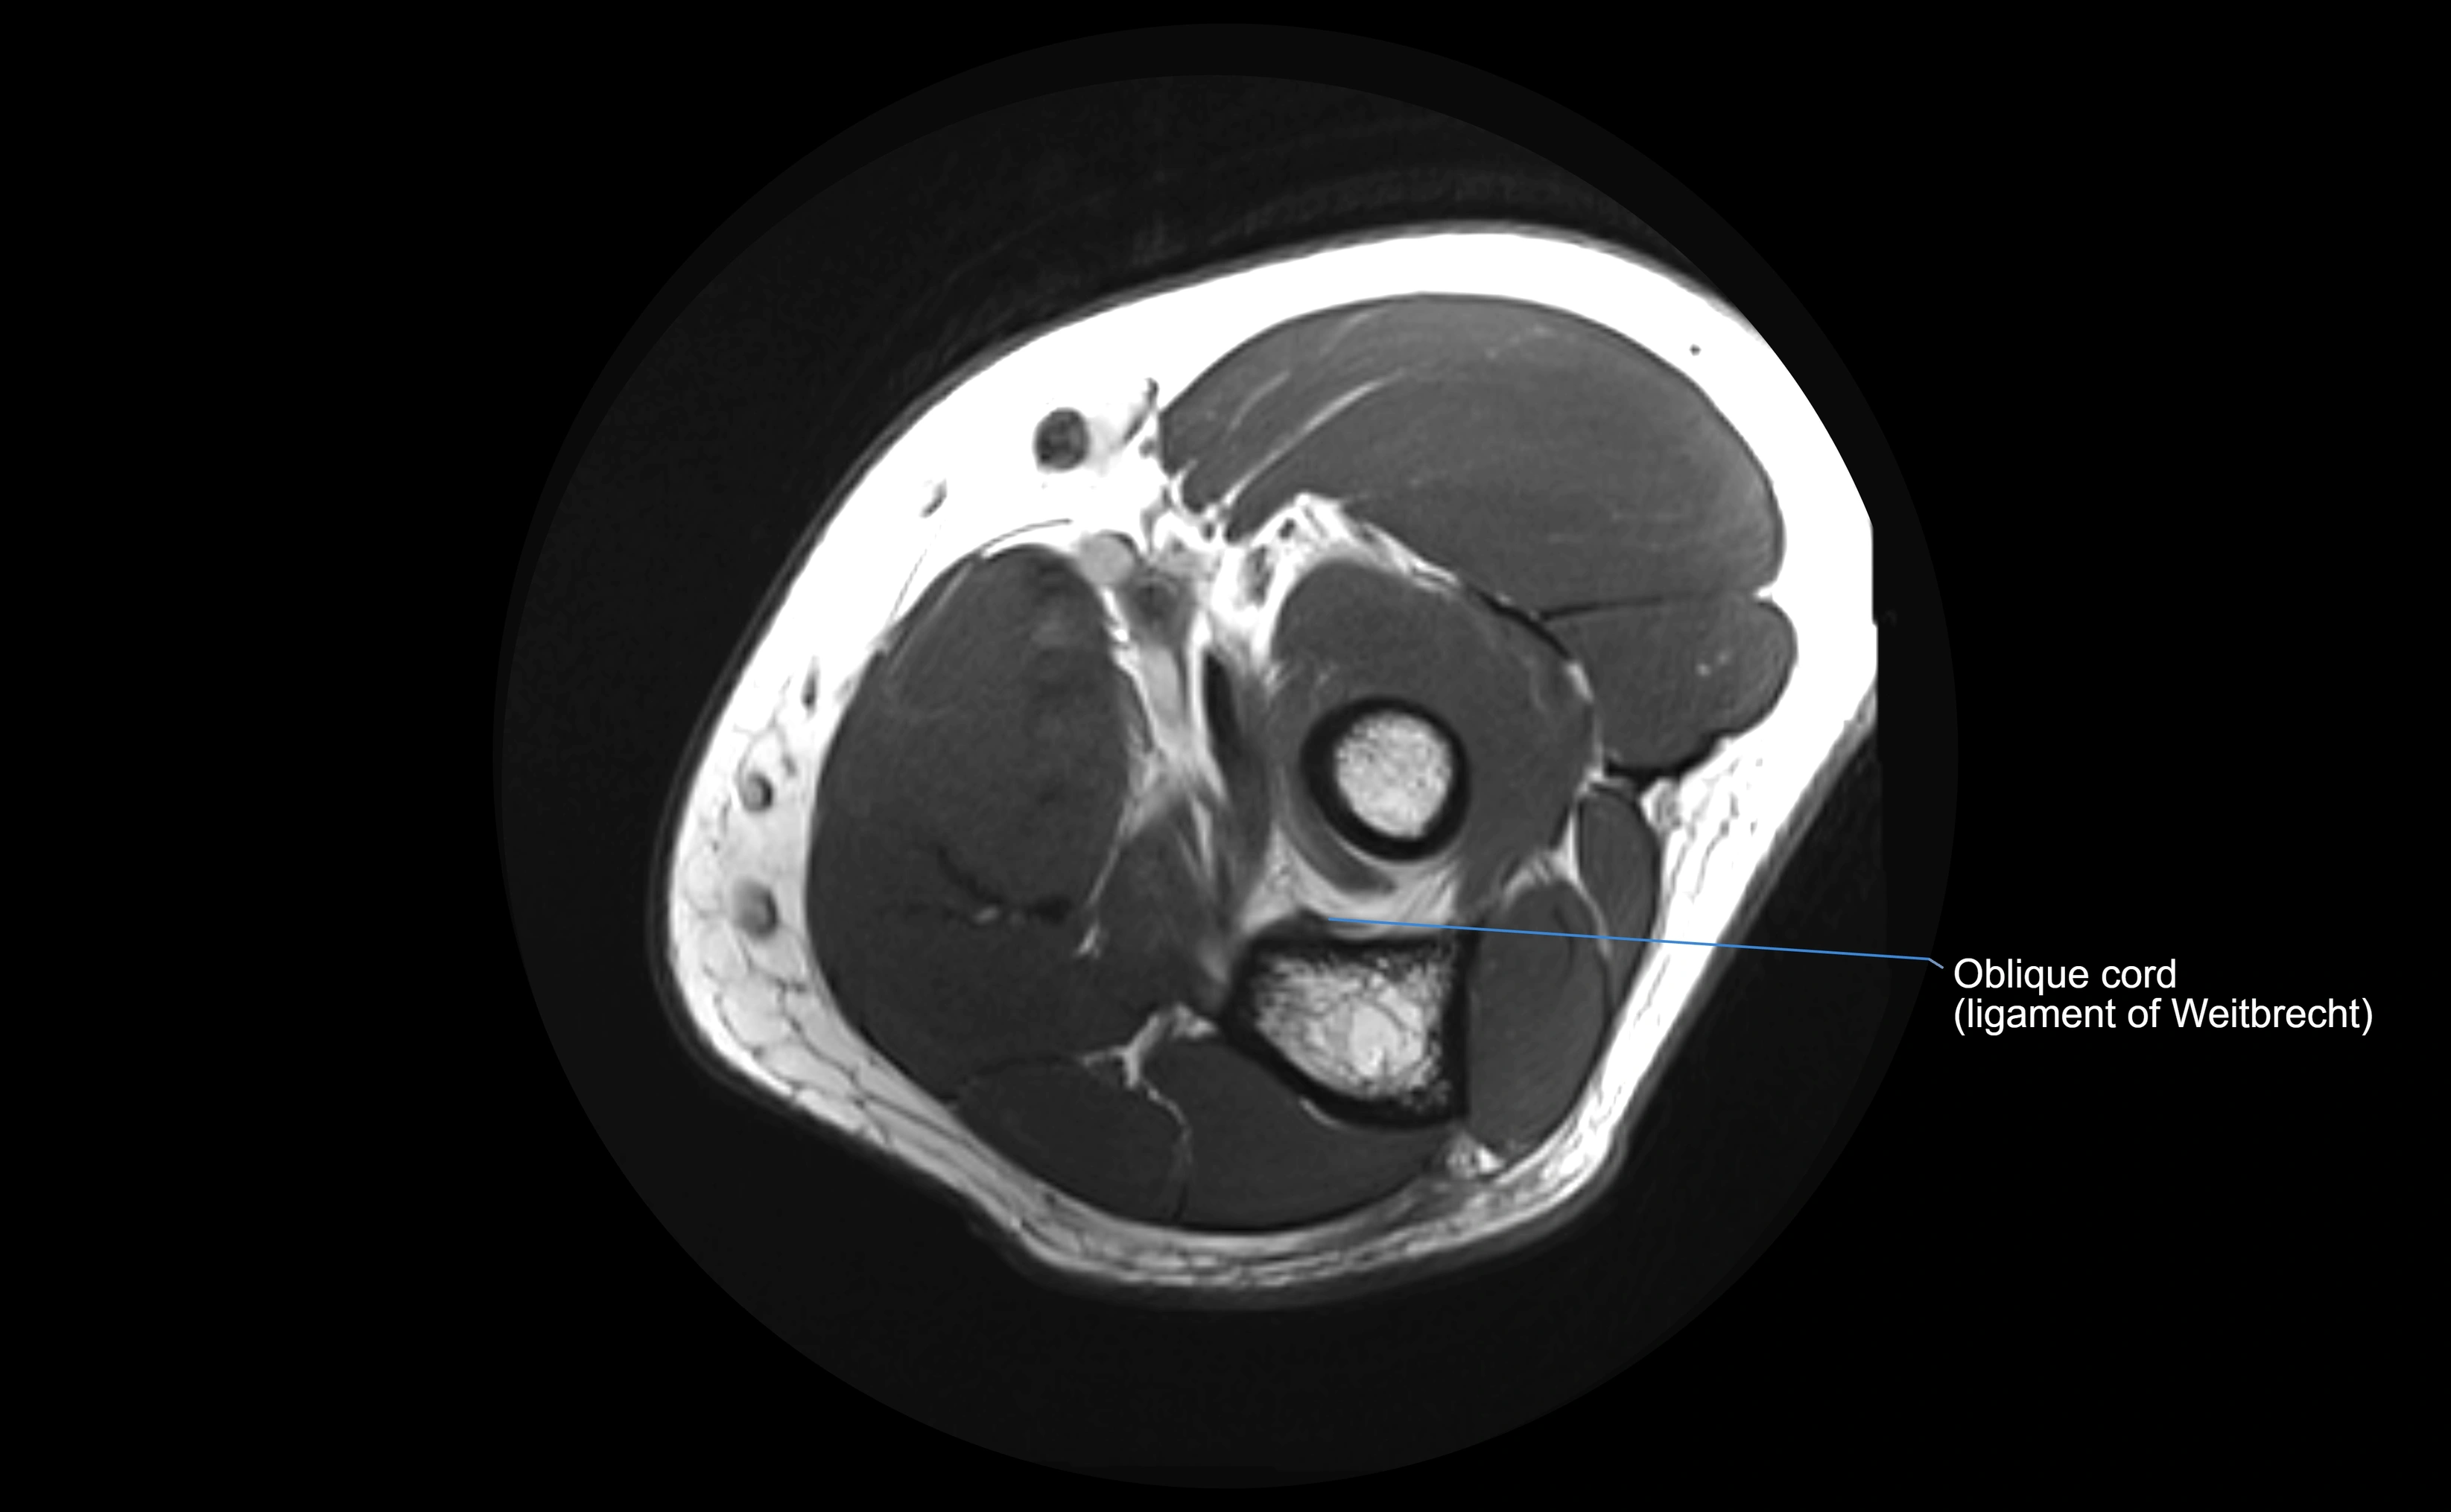

MRI images

image

• Normal ligament: dark band encircling radial head.

• Pathology: bright hyperintense periligamentous signal suggesting edema, sprain, or partial tear.

Proton Density Fat-Saturated (PD FS):

• Normal: dark, well-defined band outlining the radial head.